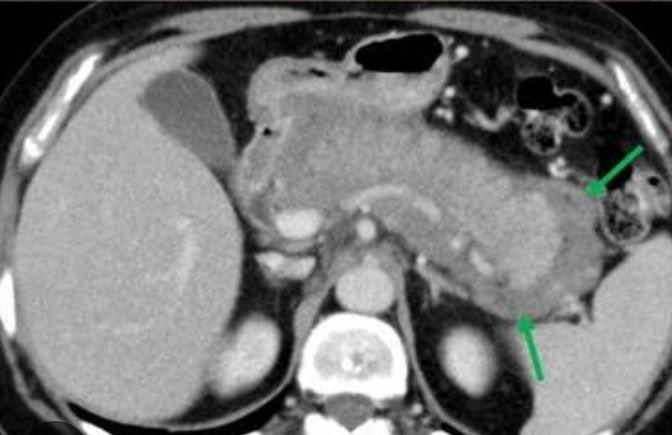

من روتايشن الامراض المعدية: تعرفون وش اسم الاختبار ؟! ووش اسم ال bacteria اللي ممكن تسوي liver abcesss ويكون فيها ايجابي ؟؟! الصعوبة: مليون ⭐️⭐️⭐️⭐️⭐️⭐️⭐️⭐️⭐️⭐️⭐️